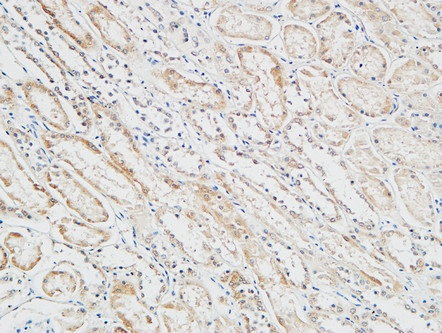

分类: 科研抗体货号: P23195别名: Toll-Like Receptor 13; Toll like receptor 13 antibody应用: IHC反应种属: Human,Mouse,Rat